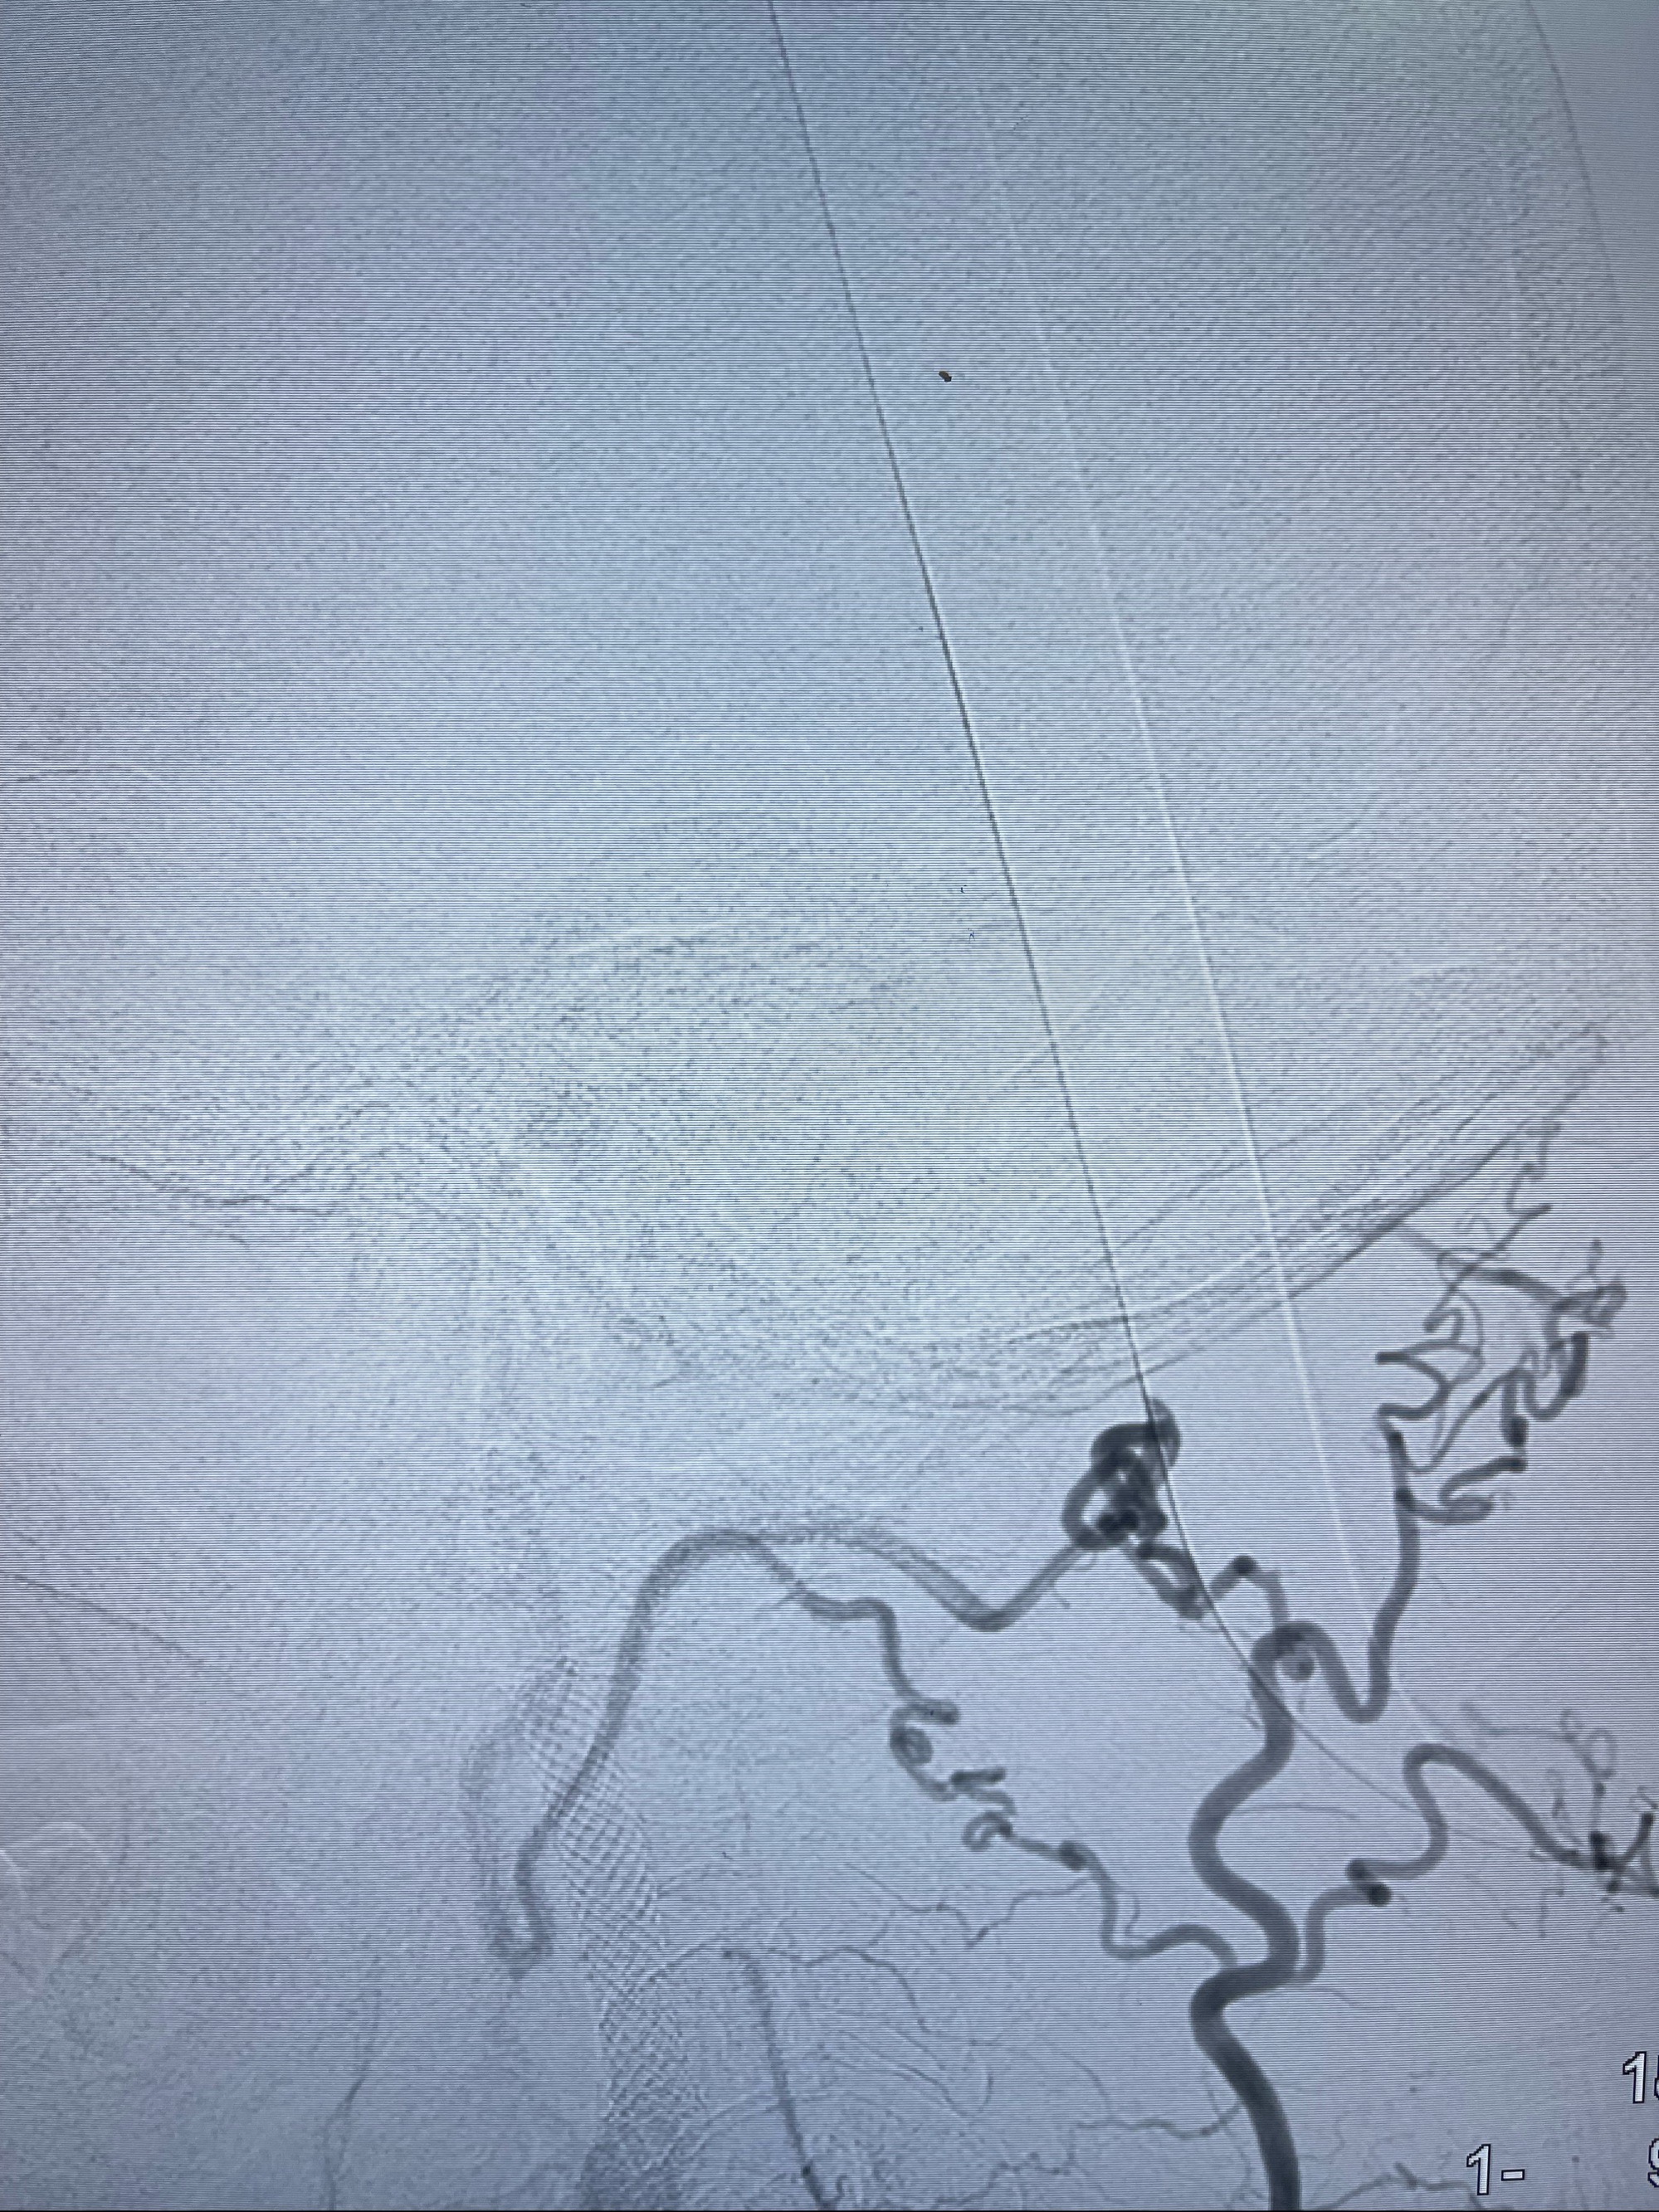

2023-07-10DSA:右侧颈内动脉岩骨段夹层伴中偏重度狭窄改变,左侧颈总动脉闭塞、右侧颈外动脉由右侧肋颈干甲颈干吻合代偿

箭头所示为颈内动脉岩骨段重度狭窄,结合MRI,考虑为肿瘤侵犯右侧颈内动脉

箭头以近至支架段管腔不规则狭窄

泄除球囊造影显示局部管腔扩张佳

即刻造影显示狭窄扩张佳